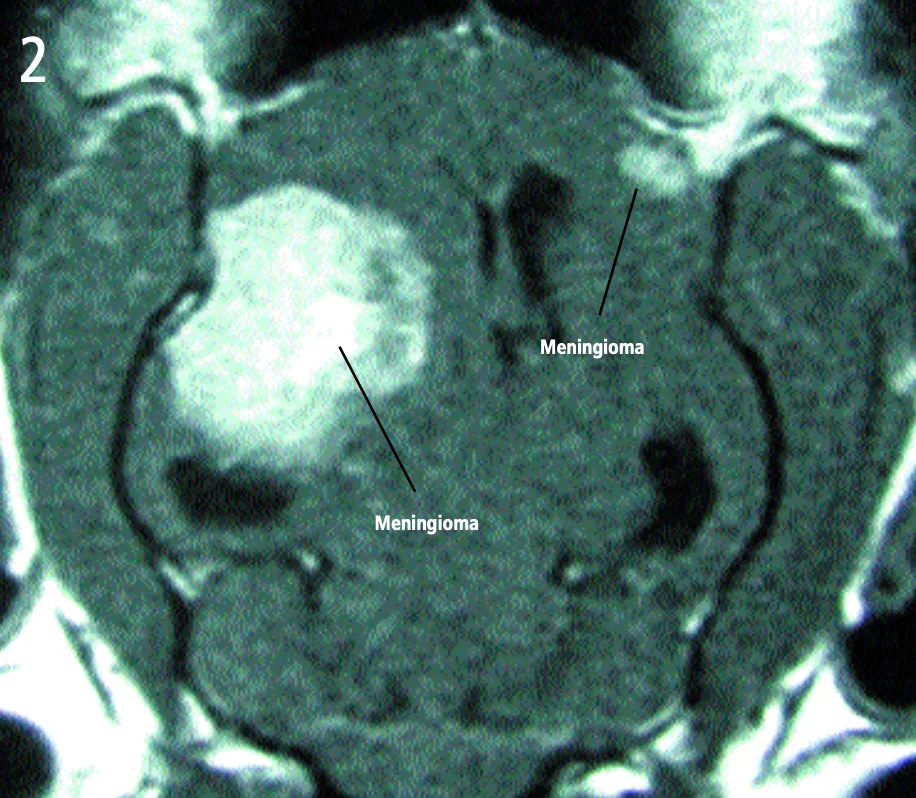

Dorsal view—T1-weighted, contrast-enhanced magnetic resonance image

A large, left-sided cerebral mass, evident on both images.

The mass is uniformly contrast-enhancing on the MRI, appears to have a broad-based attachment to the skull, and has distinct margins-all of which are characteristic of intracranial meningiomas. The most likely diagnosis is meningioma. A smaller, right-sided mass can be seen on the dorsal image. This mass also has characteristic features of meningioma. Both masses were removed and confirmed histologically as meningiomas. The cat made a full recovery.

Dorsal view—T1-weighted, contrast-enhanced magnetic resonance image